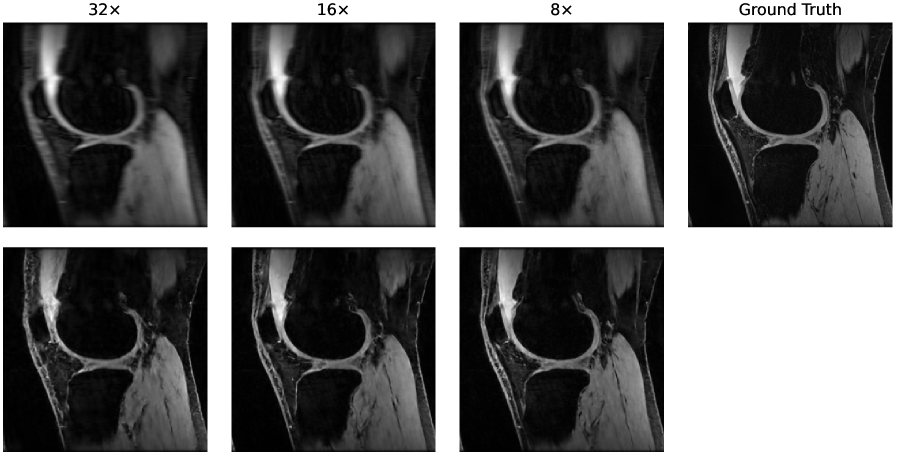

4.1 Reconstruction and Segmentation Performance

To validate the underlying models, we evaluated reconstruction quality using the Structural Similarity Index (SSIM) and Peak Signal-to-Noise Ratio (PSNR), and segmentation accuracy using the Dice Similarity Coefficient (DSC). For the DSC computation, we first calculated the average DSC score across all segmented structures for each patient, and then averaged these scores across all patients. Figure 2 shows that for both datasets, all metrics improved as the acceleration rate decreased, with the highest scores achieved in the fully-sampled setting. This trend is expected, as more k-space data provides more information for both reconstruction and the downstream segmentation task.

We also observed that performance on the CINE dataset was notably lower than on the SKM-TEA dataset across all acceleration factors. This difference can be attributed to the more challenging VISTA undersampling pattern used for the CINE data, which tends to produce stronger aliasing artifacts in zero-filled images compared to the Poisson-disk sampling used for SKM-TEA.

4.3 Qualitative Results

To provide a qualitative understanding of our dynamic stopping mechanism, Figures 4 and 5 show representative cases of both early and late scan terminations. Each figure visualizes the evolution of the reconstruction, segmentation, and the downstream metric along with its calibrated uncertainty as more k-space data is acquired. As expected, we observe a consistent trend across all examples: as the acquisition progresses, reconstruction quality and segmentation accuracy visibly improve. Moreover, the prediction uncertainty decreases the more k-space data is being collected. Additional reconstruction examples are displayed in Figure 6 and 7. Concurrently, the downstream metric estimation converges toward the ground truth value while the corresponding uncertainty bands narrow. Crucially, instances of high uncertainty consistently correspond to visible artifacts, segmentation errors, and larger deviations in the final metric, confirming that our uncertainty estimates effectively track acquisition quality.